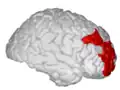

Middle frontal gyrus

Middle frontal gyrus of the human brain. | |

The middle frontal gyrus makes up about one-third of the frontal lobe of the human brain. (A gyrus is one of the prominent "bumps" or "ridges" on the surface of the human brain.)

The middle frontal gyrus, like the inferior frontal gyrus and the superior frontal gyrus, is more of a region in the frontal gyrus than a true gyrus.

The borders of the middle frontal gyrus are the inferior frontal sulcus below; the superior frontal sulcus above; and the precentral sulcus behind.[1]

Position of middle frontal gyrus (shown in red).